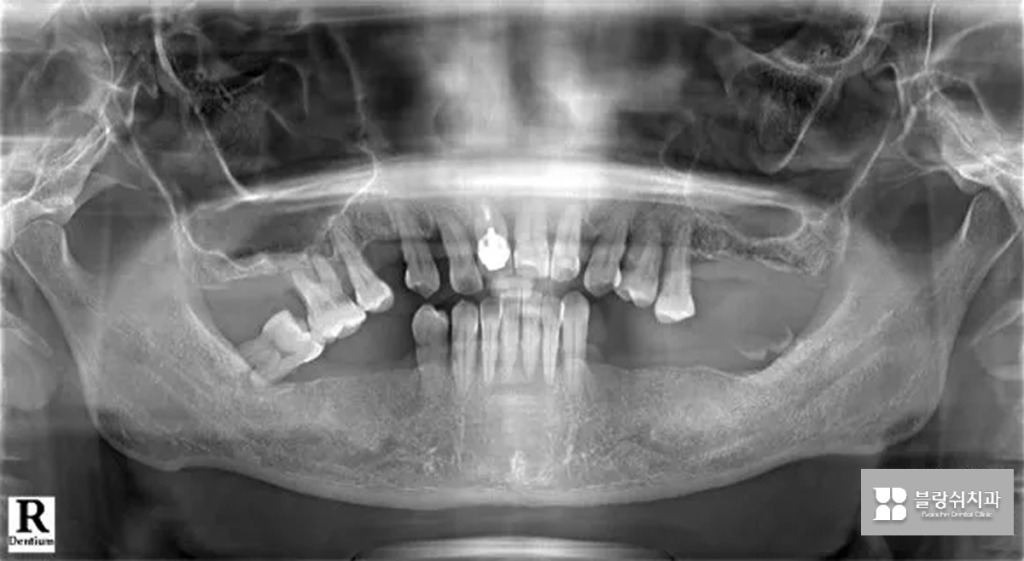

이 환자분은 아래턱 잇몸뼈가 부족한 상태로 내원하셨습니다. 단순히 임플란트만 심기 어려워서 뼈이식이나 치조골을 넓히는 작업이 필요한 상황이었고, 치아 배열이 무너져서 제대로 씹기 어려운 상태였어요.

특히 위쪽 어금니가 오랫동안 없었던 탓에 아래 어금니들이 위로 솟아오르는 현상(정출)이 생겼고, 이 때문에 위아래 치아가 제대로 맞물리지 않아 음식을 씹기가 매우 불편한 상태였습니다.

초기 상태를 보면 치석이 치아를 덮을 정도로 잇몸 염증이 심했고, 치아가 흔들리며 붓고, 시리고, 출혈까지 동반된 상황이었습니다. 가능하다면 자연치를 살리는 게 최선이지만, 이미 잇몸과 뼈가 회복 불가능한 수준까지 손상된 치아였기 때문에 더 큰 문제를 막기 위해 발치를 결정했고, 이후 임플란트로 치료 방향을 잡았습니다.